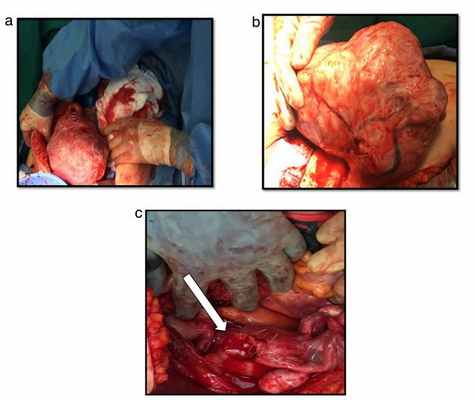

а) некротизированный миоматозный узел

б) вывернутая шейка матки

а) матка

б) область наружного зева шейки матки

в) перевернутая шейка матки

г) лейомиома

а) нормальный миометрий и полость матки

б) перевернутая шейка матки

в) миома шейки матки